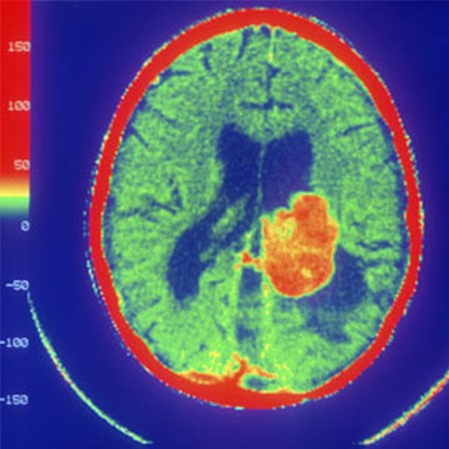

Theo giới chuyên gia, hiện nay có tới 5 - 6 loại virut khác nhau như virut sởi, đậu mùa, đang được nghiên cứu và thử nghiệm trên thế giới về khả năng gây nhiễm và phá hủy các tế bào ung thư. Dùng parvovirus - một loại virut gây viêm nhiễm, phá hủy thành mạch máu để chữa trị ung thư glioblastomne - khối u trong não. Kết quả cho thấy, trong một số trường hợp, virut đã trừ khử được hoàn toàn khối u, nhưng trong một số trường hợp khác thì hoạt động của virut lại chưa đủ mạnh.